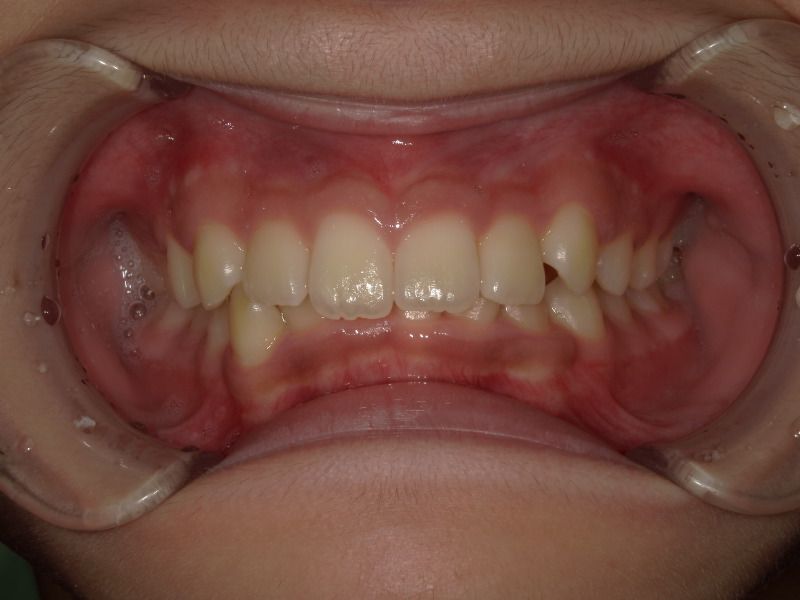

始めの検査の時の写真です。

下の歯があまり見えておらず、横からの写真を見ると上の歯に覆い被さっているように見えます。

上の歯の矯正

過去にこの男の子は他院で上の歯並びのみ矯正をしていました。

確かに上の歯は綺麗ですが、下の歯にはガタつきが残っています。